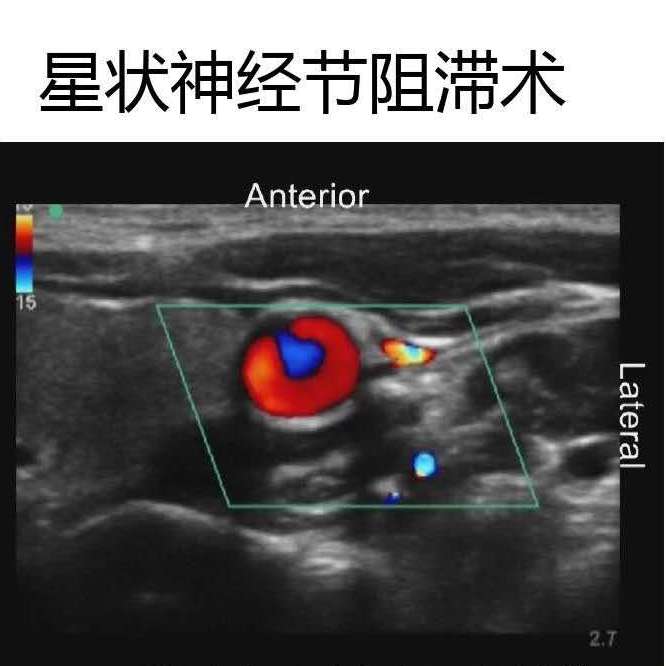

如星狀神經(jīng)節(jié)阻滯術

超聲多普勒技術可以清楚的觀察到血管

提高對于局部解剖的觀察

(神經(jīng)及周圍結構的回聲表現(xiàn))